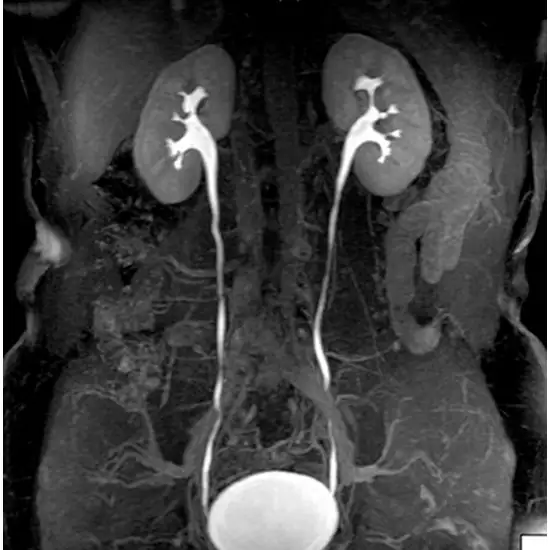

Imaging the urinary and digestive systems is done using MRI scans of the kidney, ureter, and bladder (KUB).

The MRI KUB scan is an imaging technique that produces scan images of the kidney, ureters, and bladder. The scan images are produced by using strong magnets and radio waves.

MRI KUB scan images show the urinary system, which helps in visualizing calcifications in the ureters, bladder, urethra, or kidneys. It can also help to confirm any obstruction, stones, or abnormal growth of the renal tract.